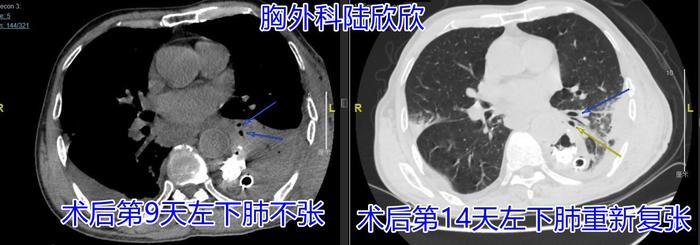

术后患者心脏不太好,但是咳嗽咳痰较好。但是几天以后,患者错误的认为自己每天只有两口痰,每天早上患者雾化吸入以后,咳出两口淡黄色粘痰以后,就认为一天的任务结束了,就不咳嗽了。我和病人的妻子来回劝,病人根本听不进去。又过来几天病人出现胸闷,再出现低烧,不超过37.5度。急诊CT检查发现患者有左下肺不张,左下肺被痰液堵塞后塌陷了

上图为图6。为术后第九天的CT。可见两个蓝色箭头指示的是左下叶支气管,再往下支气管就被堵死了。黄色箭头指示的是肺不张

经过我的两次床旁气管镜吸痰,病人受了罪,痛改前非,知道自己痰液每天不是固定两口,每天努力咳嗽咳痰了。

上图为图7。左图是为术后第九天的CT。可见两个蓝色箭头指示的是左下叶支气管,远端肺不张。右图是为术后第十四天的CT。可见两个蓝色箭头指示的是左下叶支气管,远端肺重新复张